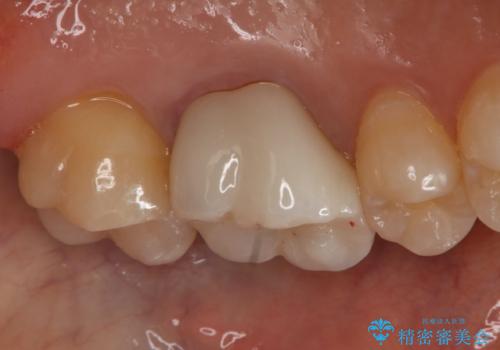

銀歯を白くしたい セラミックインレー

- 左上7番の銀歯をセラミックにやり変え希望の患者様です。

切削量・形態からセラミックインレーでの治療を計画しました。

銀歯とその直下のう蝕を除去した後、CRにて裏層しています。

インレー装着の際はラバーダムを使用しています。